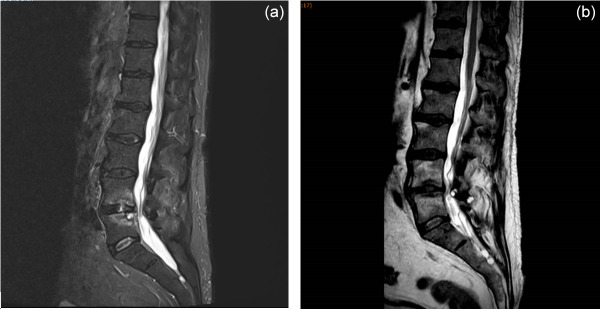

Rezafungin, which only requires weekly administration, is a potential candidate for difficult-to-treat infections that require long-term antimicrobial treatment, such as bone and joint infections. We report the first case of Candida glabrata spondylodiskitis successfully treated with 3 weeks of caspofungin followed by 10 weeks of rezafungin.